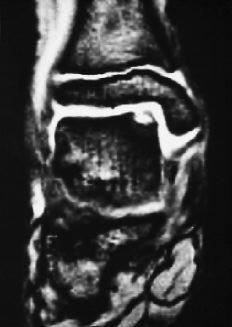

En los 64 pacientes se pudo realizar el diagnóstico en 63 casos mediante radiografías del tobillo, predominando las zonas claras (56%) y observando cuerpos libres en sólo tres ocasiones (5%) (Fig. 2). En la radiología postoperatoria se observaron dos datos interesantes; el primero es que en 18 casos (28%) había ausencia de lesión osteocondral en la fase de seguimiento, mientras en los demás existía bien una zona clara (19 casos) o irregularidades en el contorno articular con depresiones o impresiones de ésta (24 casos) (Fig. 3). En 16 casos se realizó una RM y en cuatro se realizó una TAC. El objeto de estas exploraciones fue el obtener más información sobre el estado de la lesión, con excepción del mencionado caso en el que radiográficamente no se pudo ver la existencia de dicha lesión y cuyo diagnóstico se hizo a través de la RM.

En cuanto al pronóstico del tratamiento quirúrgico de estas lesiones hay que señalar que cuanto más avanzada sea la edad del paciente o el grado de la lesión según la clasificación intraoperatoria peores serán los resultados finales (Fig. 7). La localización desempeña también un papel importante, siendo las lesiones laterales, en su mayoría ventrales (fuera de la zona habitual de carga), las que presentan un mejor pronóstico.

ABCFigura 7. Paciente de 11 años de edad. A: Rx preoperatorias. B: RM. Radiológicamente se consideró un Grado 3 a 4 de lesión. Intraoperatoriamente se encontró un reblandecimiento del cartílago, demarcado y sin fisuras. Se hizo una perforación retrógrada bajo control radiográfico y artroscópico. C: Resultado final tras 3 años de seguimiento; la paciente está asintomática.